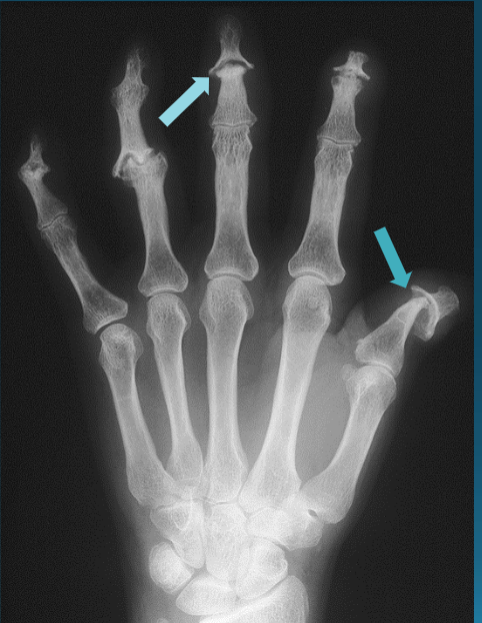

Swan neck deformity, Boutonniere deformity, Ulnar Deviation

Psoriatic Arthritis

Can affect DIPs (unlike RA)

Arthritis mutilans subtype (very rare)

DIP Involvement → Pencil in Cup Deformity